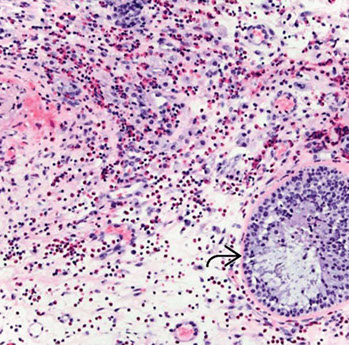

Angiocentric T-cell lymphoma (NT/NKCL)

- formerly “lethal midline granuloma.”

Nasal T-cell/natural killer cell lymphomas  characterized by extensive facial swelling, deformity,

ulceration and necrosis. Nasal septal perforation and

collapse of the nasal bridge may occur

-largely 2/2 angiocentric tendency of these lymphomas

- classic features: angiocentricity with massive

necrosis

- angiocentricity is not required to dx

Micro: spectrum is wide small, medium, or large cells, or a mixture of cell types

- mixed pattern may be mistaken for reactive inflammatory infiltrate

IHC: (+) EBV, CD56, CD45/2/3e(cytoplasmic), perforins

- neg: EMA, CK, SYN, CHR, pan-T cell markers (CD3)

Genes: FISH >80% c EBV assoc nuclear

RNA (EBER)

Px: linked to stage, but T-cell sinonasal lymphomas

had, after radiotherapy, 5 – and 15-year survivals of 63% and 50%. NT/NKCL patients may develop

hemophagocytic syndrome.

Extranodal NK/T cell lymphoma, nasal type